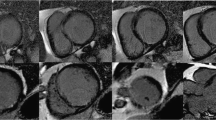

LGE imaging is mandatory for differential diagnosis between forms of cardiomyopathies, because enhancement patterns may address distinct conditions. In traditional LGE imaging, the inversion time (IT) to null the signal of healthy myocardium is manually chosen by the operator using a specific sequence (Look Looker, for instance). The choice of the optimal IT is crucial to obtain maximum contrast between pathologic and normal cardiac tissue. This operator-dependent choice might be challenging in case of massive infiltration of the heart, for example in case of amyloidosis, and may result in erroneous choices resulting in non-diagnostic examinations (Fig. 1) [4]. The introduction of phase-sensitive inversion recovery (PSIR) sequences by all vendors, a LGE reconstruction technique less sensitive to operator choice of IT, has made it easier to obtain accurate LGE images and to determine the extent of cardiac involvement [5].

57-year-old patient with multiple myeloma with known bone lesion associated with light chain proteinuria and bilateral carpal tunnel syndrome. Cine-SSFP sequences (a short axis view; b 4-chamber view) showed a thickening of the left ventricular myocardium wall (19 mm in the septum) with global and moderate hypokinesia (left ventricular ejection fraction 46%). In panel c are reported some of the images of the lock–locker sequences of the TI scout. Inversion recovery turbo field echo sequences (d and e short axis view; f and g 4-chamber view) with a wrong myocardium null time (red box and arrow) and the one with the correct null time (green box and arrow); these last showed a diffuse areas of circumferential subendocardial pattern enhancement. The final diagnosis was light chain (AL) cardiac amyloidosis

LGE imaging with inversion recovery sequences is a fundamental technique to diagnose CA [11]. LGE imaging requires to set a proper inversion time to null the signal of healthy myocardium. This can be challenging in CA because of an accelerated clearance of gadolinium occurring when it encounters amyloid fibrils, or in case of diffuse infiltration, resulting in the difficulty of nulling myocardial signal before blood pool (Fig. 1). Such occurrences are highly suggestive for CA. The introduction of PSIR, an LGE technique less sensitive to operator choice of null point, has made LGE easier to perform on CA patients [13]. Three LGE patterns have been described: absent, diffuse subendocardial and transmural [13]. These patterns are correlated with the degree of infiltration of the LV and provide prognostic information, since a greater burden of infiltration is related to poorer prognosis [12].

83-year-old male patient with known CAD and the presence of dyspnoea. Cine-SSFP sequences (a short axis view; b 4-chamber view), which show a thickening of both the left ventricular myocardium (18 mm in the septum) and the right ventricle, but also of the atrial walls with global and severe hypokinesia (left ventricular ejection fraction 26%). Inversion recovery turbo field echo sequences (c short axis view; d 4-chamber view) for late gadolinium enhancement (LGE) analysis; there are diffuse areas of circumferential subendocardial pattern enhancement even with transmural extension in the basal segment. There is also LGE within the right ventricle and both atrial walls. The quantitative evaluation of global left ventricular myocardium native T1 (e short axis view) and ECV (f short axis view) resulted in 1110 ms (v.n. 1000 ms) and 55% (v.n. 20–30%), respectively. Overall, the presence and the pattern of LGE with a transmural pattern in both ventricle and atrial walls were suspicious of transthyretin (ATTR) amyloidosis. The patient was then scanned with 99mTc-DPD (image g), where the abnormal and diffuse presence of the osteotropic indicator is observed in the left and right ventricle with a Perugini score = 3. The final diagnosis was ATTR amyloidosis